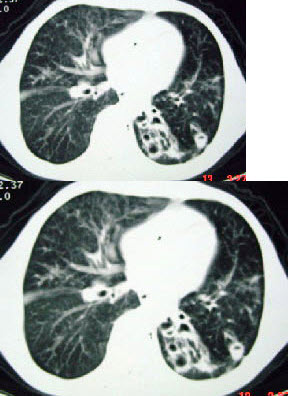

27、单项选择题

女,32岁,鼻梁双颊部出现红斑伴发热咳嗽2周,肘腕关节游走性疼痛,请结合CT,选择最可能的诊断为()

A.肺部感染

B.结节病

C.肺类风湿病

D.SLE肺部浸润

E.韦格肉芽肿